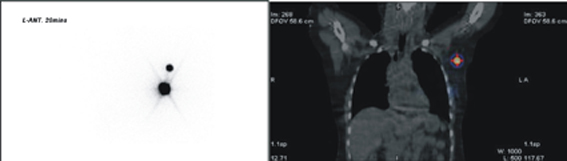

圖三、前哨淋巴結攝影。左圖為平面靜態攝影,可見藥物注射處以及前哨淋巴結;右圖為單光子斷層掃描造影,顯示左側腋下前哨淋巴結位置。本院核子醫學科統計自2013年1月到9月之間本院受檢的病患,發現單光子電腦斷層掃描可使前哨淋巴結定位率由90%上升至96%。此詳細的定位對外科醫師手術有很大的幫助。